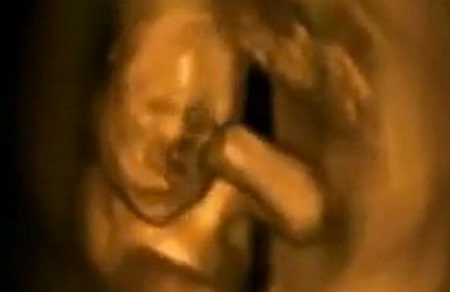

On the move: The foetus looks at times like it's dancing and waving on the ultrasound scan

This video of an unborn baby has had more than six million views because the little one looks like it's dancing in the womb.

The amazing footage is from a 4D ultrasound scan and it really looks like the foetus is bopping away inside its expectant mum, although no more is known about her identity.

While many of us are familiar with 3D ultrasound images which show still images of unborn babies, 4D scans can show moving 3D images.

The foetus is seen in a variety of positions, moving its limbs and even kicking out against the womb, before giving what looks like a big yawn.